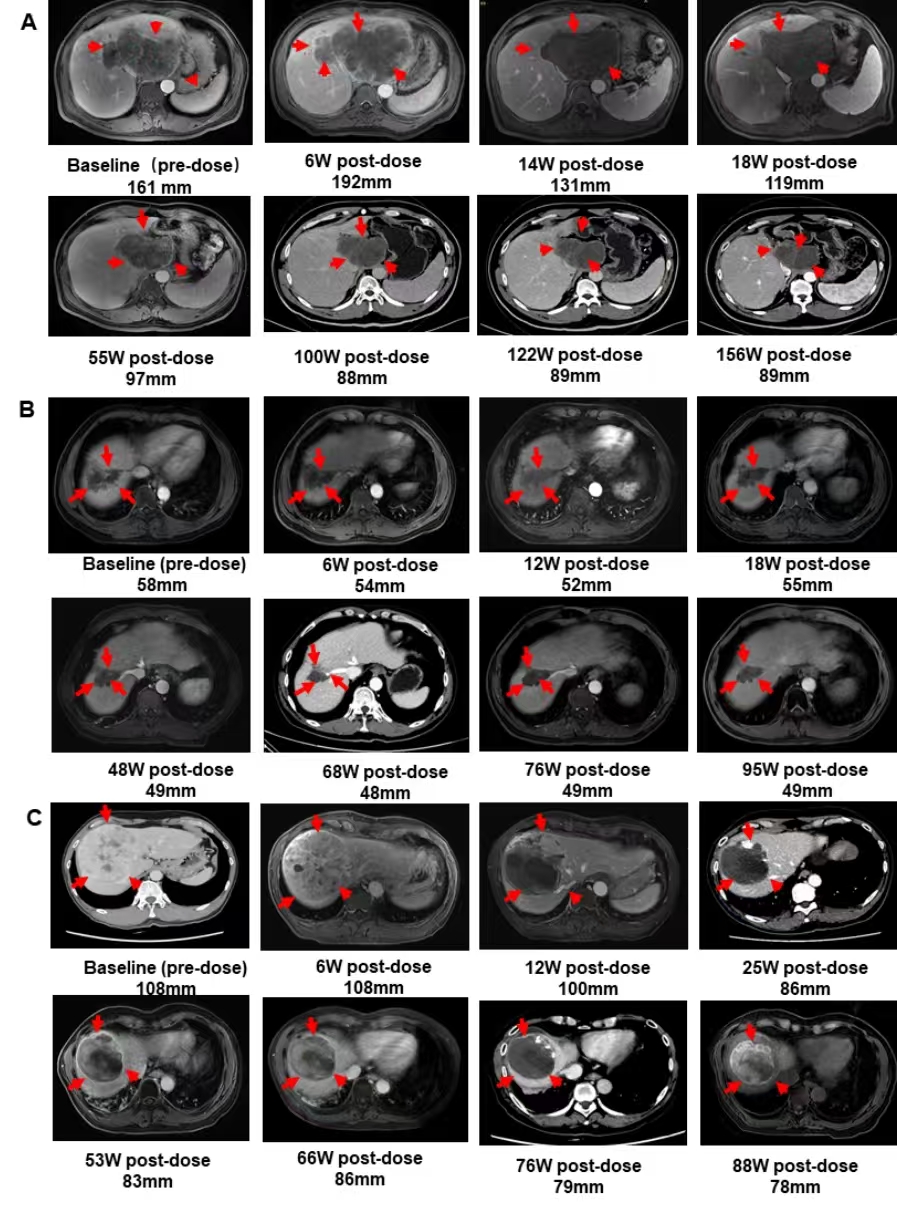

中山大学附属医院研究团队开展的临床研究证明:溶瘤病毒M1-c6v1联合卡瑞利珠单抗(抗PD-1)和阿帕替尼在晚期肝细胞癌中是一种具有临床前景的治疗策略。该研究共13例患者接受了治疗,10例患者被纳入疗效分析。结果显示:用mRECIST标准评估肿瘤反应时,客观缓解率为70%,疾病控制率为80%,中位无进展生存期(mPFS)为8.9个月,中位总生存期(mOS)为15.4个月。截至2025年5月31日,有3例患者(N09、N11和N14)仍然存活,其生存时间分别为44个月、40个月和38个月。停止M1-c6v1治疗后的两年多时间里,三名患者的肿瘤状态基本保持稳定。